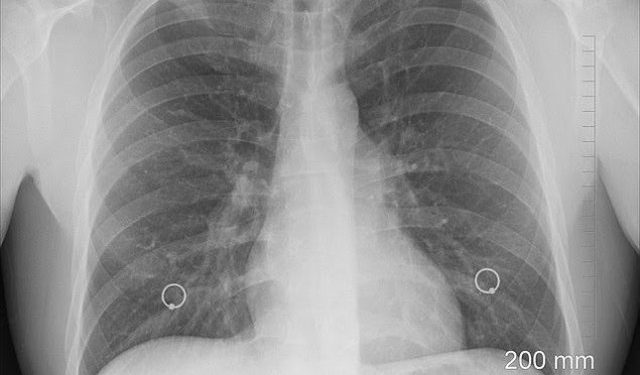

Në një studim të gjerë, studiuesit analizuan të dhëna nga 27.795 pacientë të diagnostikuar me kancer të mushkërive nga 2000 deri në 2017, dhe arritën në përfundimin se treguesit më të hershëm të sëmundjes ishin gulçim dhe një kollë e gjatë, sado e butë të jetë ajo.

Më parë, simptoma e parë e kancerit të mushkërive ishte kollitja me gjak, por është një koncept i vjetër dekada dhe në disa kancer kjo simptomë shfaqet vetëm në fazat e vona të sëmundjes.

Njohja më e mirë për simptomat, të cilat do të ndihmojnë në zbulimin e hershëm të sëmundjes dhe rritjen e shanseve të kurimit, është thelbësore, sipas mjekëve britanikë në revistën ‘Royal Society of Medicine’.

Sipas disa vlerësimeve, kanceri i mushkërive në fazën e hershme është i shërueshëm në 50 për qind të rasteve, domethënë jeta mund të zgjatet, ndërsa shërimi në atë që tashmë është metastazuar është më pak se 5 për qind.

Shqetësimi është i nevojshëm nëse keni një kollë të vazhdueshme, me dhimbje në gjoks, lodhje dhe humbje të energjisë dhe humbje peshe, transmeton KosovaPress.